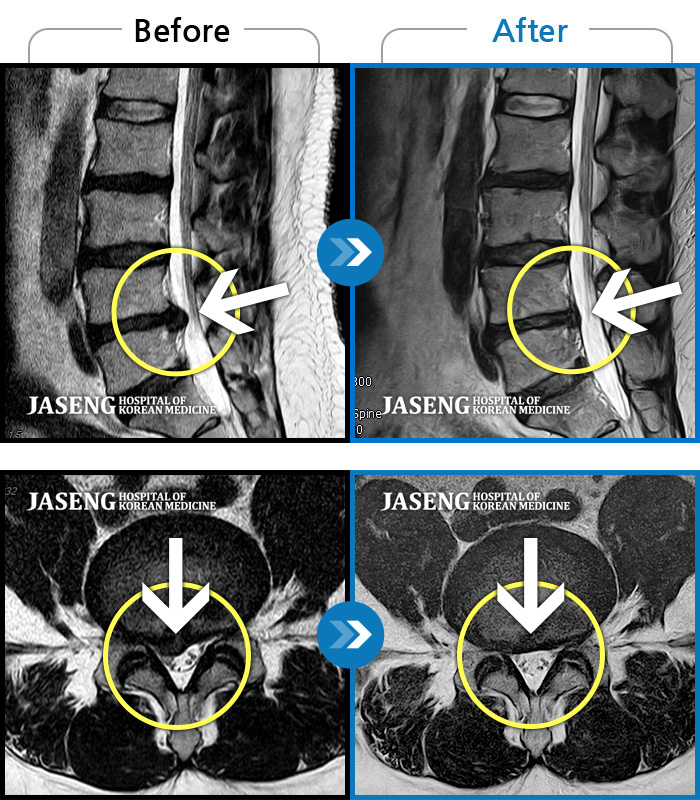

목디스크

강남 · 강만호 원장

양측 승모근 통증과 목 통증, 견갑골 통증으로 고개를 돌릴때 통증을 호소하는 환자였습니다.

촬영시기

2019.11.18 ~ 2024.07.30

2024.08.09